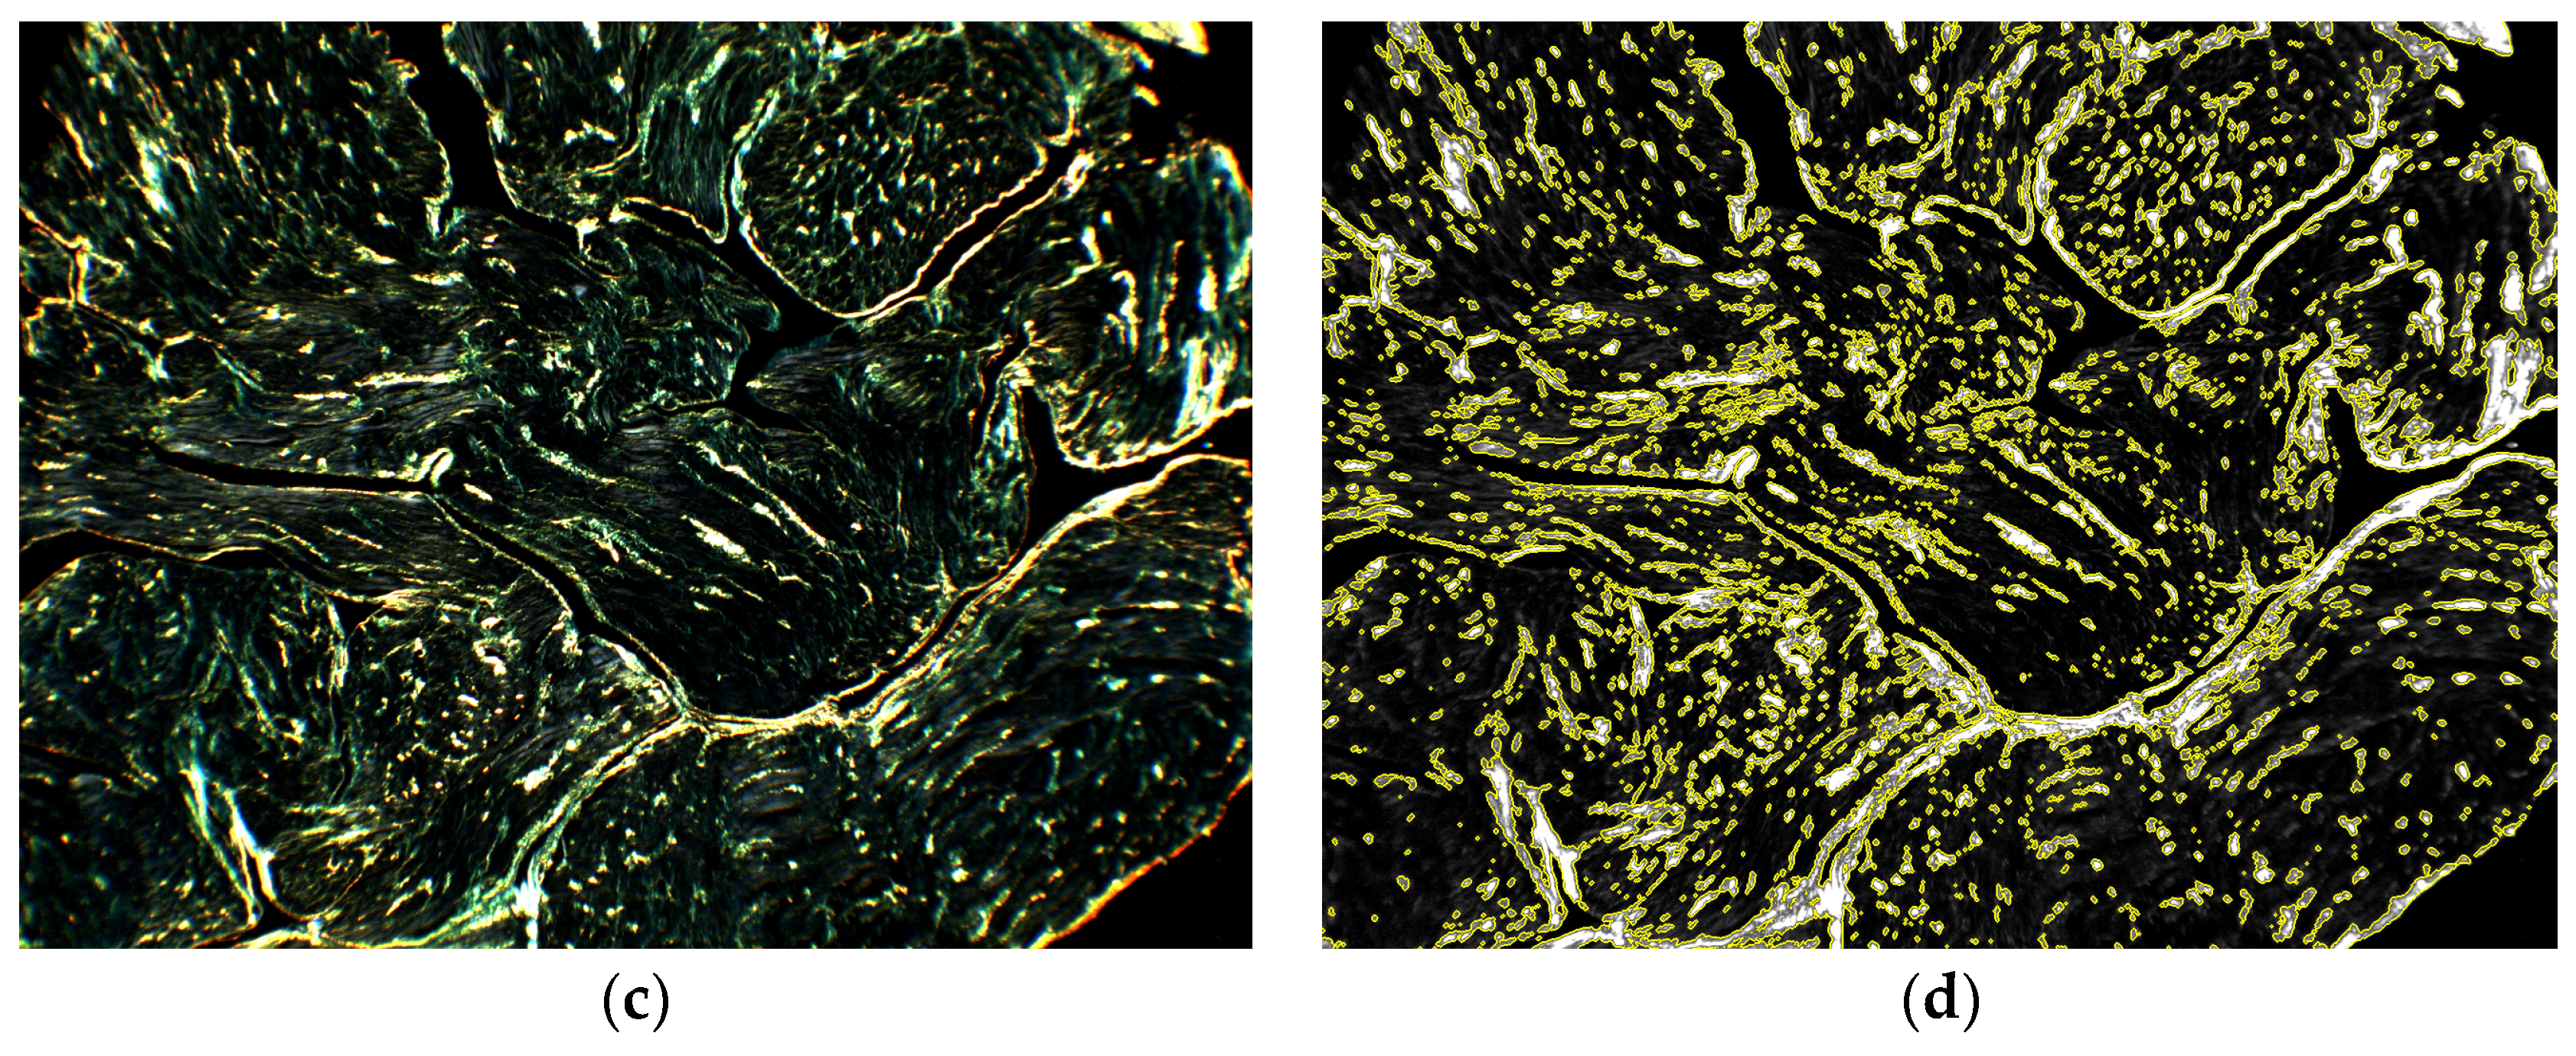

Figure 5 shows an example of the algorithm capability to compensate artifactual variability related to sample thickness. Two spatially close tissue sections, characterized by similar tissue composition but different thickness, were compared. At visual inspection, the tissue profile and the red stain distribution followed similar patterns, while the different section thickness affected the transmittance values (Figure 5a,b). In the original dark-field images, a difference in birefringent signal intensity was observed (Figure 5c,d), where the thicker section emitted a redder and more intense birefringent light. After thickness correction, the RGB birefringence images (Figure 5e,f) were more balanced in terms of intensity and chroma. The threshold = 0.152 on the greyscale collagen signal (Figure 5g,h) produced comparable fractions of collagen content (8.1% and 11.1%, respectively). It is to notice that a more fragmented collagen distribution was present in the thinner section, while in the thicker one the signal formed larger clusters, probably owing to the additive effects of a larger number of myocardial tissue layers.

Figure 5.

Correction for sample thickness variability. The robustness of the algorithm against sample thickness variability is examined comparing a slice of average optical thickness = 0.36 (left column) with a nearby slice of average optical thickness = 0.21 (right column): (a,b) The sample transmittances evidences the different tissue thickness between the two samples; (c,d) Original dark-field images (windowed 0–32,768); (e,f) RGB birefringence signal images (windowed 0–0.5); (g,h) Greyscale collagen signal images (windowed 0–0.5). The collagen mask for a threshold = 0.152 is contoured in yellow. The estimated collagen fractions were = 8.1% and 11.1%, respectively.